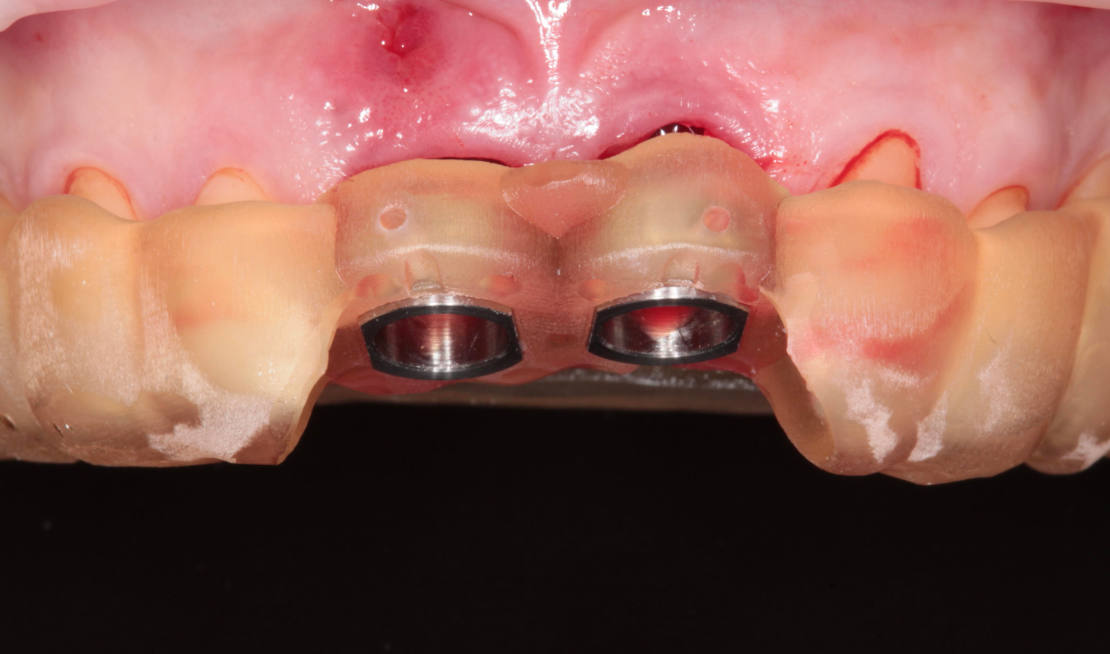

Jediným riešením bola extrakcia obidvoch zubov. Najväčšou obavou zo strany pacientky bola strata obidvoch predných zubov a následného fungovania bez nich pri práci s ľuďmi. Ideálnym riešením teda bola náhrada zubov implantátmi spolu s nasadením koruniek, a to počas jedného sedenia. V deň konzultácie bol pacientke urobený sken pomocou intraorálneho skeneru 3Shape TRIOS, ktorý nám umožňuje zobraziť 3D simuláciu ústnej dutiny. Pomocou softwaru 3Shape Implant Studio sme spojili dáta z intraorálneho skenu a CBCT, STL a DICOM súbory. V ďalšom kroku sme virtuálne vložili implantáty v správnej protetickej polohe, navrhli šablónu pre ich zavedenie, namodelovali individuálne abutmenty a korunky (obr. 4). Kompletné dáta sme exportovali pre frézovanie a 3D tlač. V laboratóriu sa pomocou 3D tlačiarne vytlačila chirurgická šablóna, ktorá nám slúži na presné zavedenie implantátov – použili sme implantačný systém Dentium Super Line. Následne boli vyfrézované zirkonové abutmenty a plastové dočasné korunky(obr. 5).

Následne sme použili protokol vŕtania a zavedenia implantátov cez šablónu (obr. 7, 8), na ktorej sme mali orientačné body pre správne napolohovanie implantátov, abutmentov a koruniek (obr. 9–14).